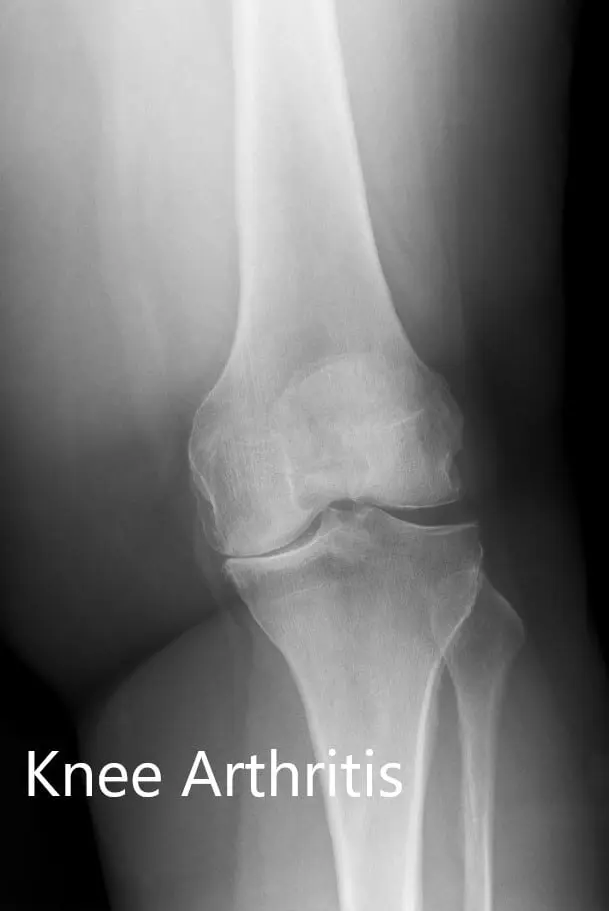

There was no distal neurological deficit and the bilateral distal pulses were comparable. The bilateral lower extremity superficial and deep tendon reflexes were positive and comparable. Imaging revealed osteoarthritis of bilateral knees (left > right). Smoking cessation education was given to the patient.

Preoperative X-ray showing the AP and lateral views of the left knee